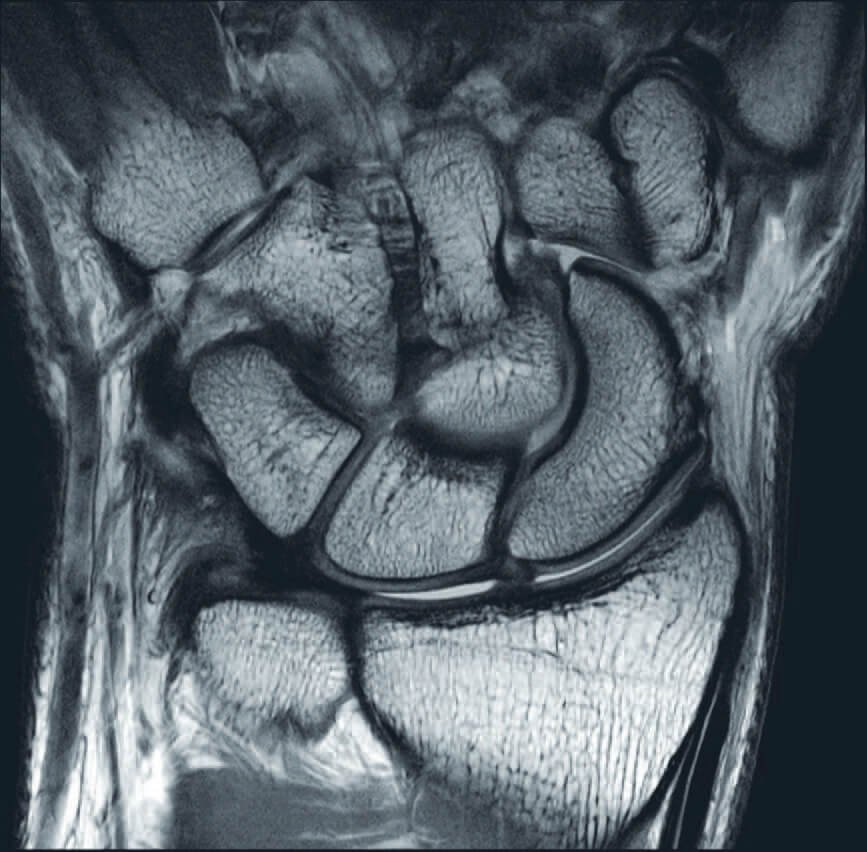

Orthopedic